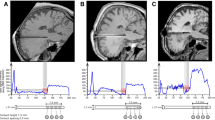

Tractography Delineation by Deterministic Tracking

Figure 2 shows the deterministic tracking result of one representative patient in two states: (a) DBS-on state and (b) DBS-off state. As seen in the representative images, only a few tracts are identified by deterministic tracking.

Illustration of the NSP, HDP, and DRTT reconstructed by deterministic tracking method in one representative patient in two states. a DBS-on state; b DBS-off state. STR striatum, THA thalamus, PG precentral gyrus, SN substantia nigra, STN subthalamic nucleus, DN dentate nucleus, NSP nigrostriatal pathway, HDP hyperdirect pathway, DRTT dentato-rubro-thalamic pathway

For both the DBS-on and the DBS-off conditions of DTI, the NSP was successfully reconstructed in most of the patients (69.6–77.4%); the HDP was reconstructed in a small proportion of patients (4.3–12.9%), and the DRTT could not be reconstructed at all. The number and percentage of patients with successfully reconstructed tractography are shown in Table 2.

No significant differences were observed in the numbers of tract count of the right NSP versus that of the left NSP (DBS-on: p = 0.183; DBS-off: p = 0.069). The numbers of NSP tract count between the DBS-on and the DBS-off states show no statistical differences in either side (right side: p = 0.476; left side: p = 0.563) as shown in Table 3.